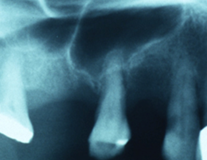

Maxillary sinus expands inferiorly and laterally after loss of posterior teeth. It may progress to take up whole posterior maxilla, and is a pneumatized with 1 to 2 mm of bone below the sinus floor. Sinus lining is raised to sandwich graft material between sinus lining and sinus floor to gain bone height to place implants in the maxillary posterior region.

(a) extreme pneumatization of the sinus with a mm of bone displayed at the sinus floor

(b) Sinus grafted and replaced with 17mm long implants